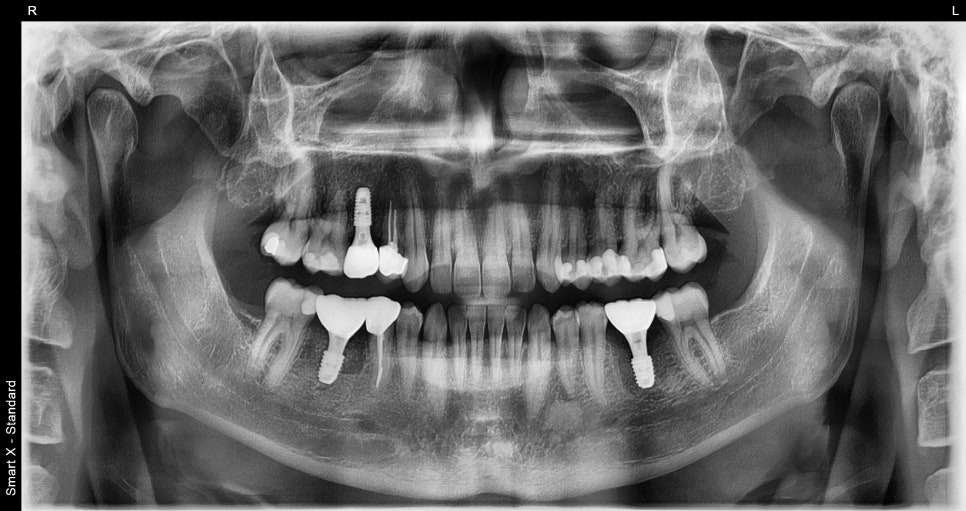

This is the initial panoramic X-ray of the patient who visited with pain after treatment overseas a long time ago.

The first large molar on the lower right had severe root apex inflammation, and the first large molar on the lower left had severe decay with crown fracture observed.